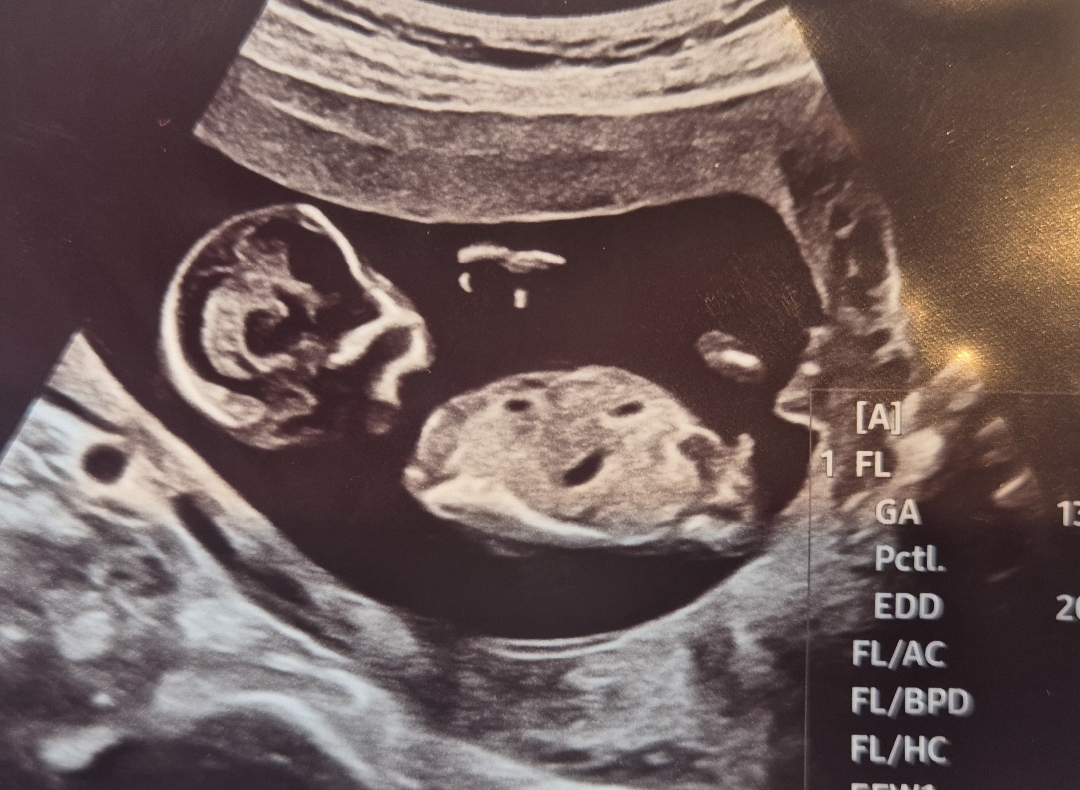

13주차 성별확인 부탁드립니다!

의사선생님은 아들같다고 하시긴했는데 혹시나.. 확정은 아니라 하셔서 의견 부탁드립니다